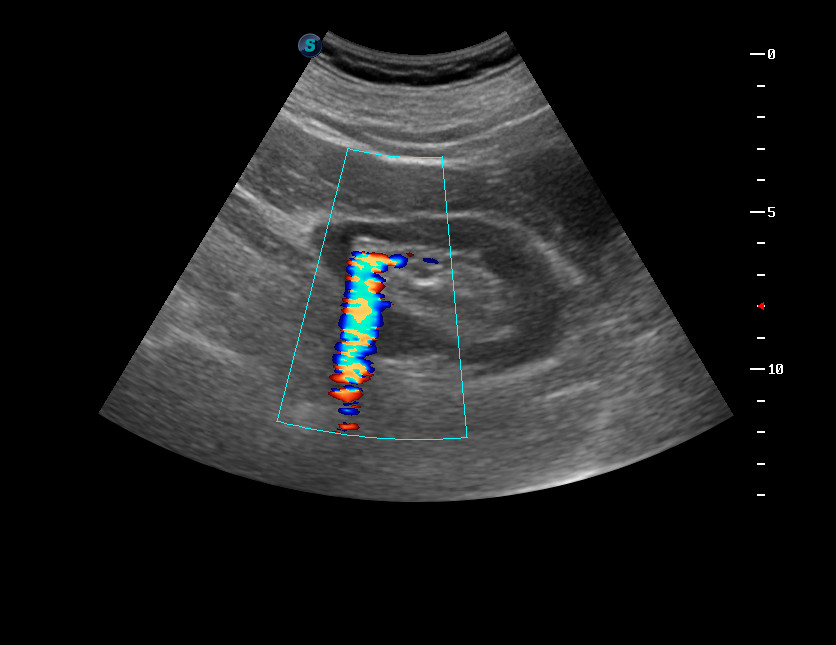

Камень почки и твинклинг-артефакт УЗИ

oct202014090925_0.jpg